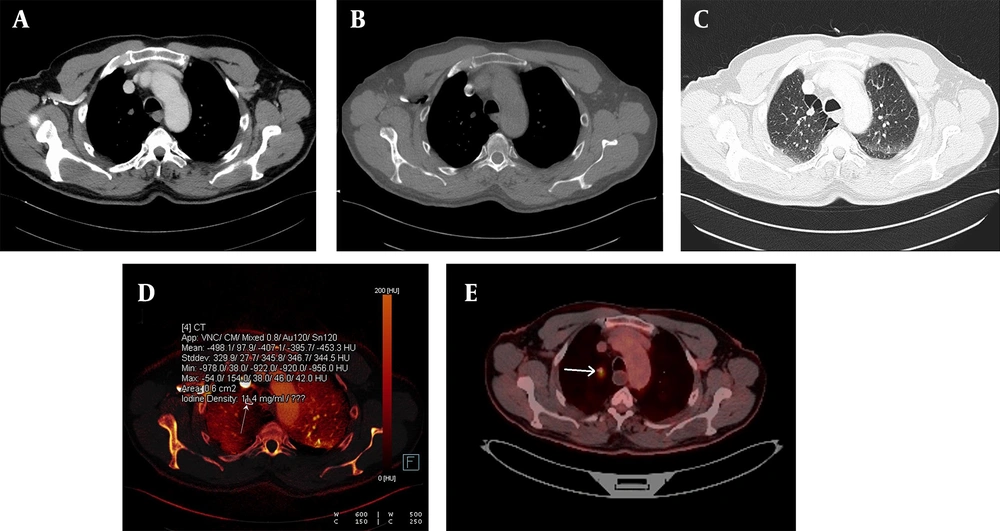

A malignant nodule is shown on an iodine-enhanced image. A, Weighted average image; B - C, Virtual non-enhanced images; and D, Iodine load in dual-energy computed tomography, DECT. In the iodine-enhanced image D, the iodine value was measured at 11.4 mg/dL. E, The malignant characteristics of the nodule were clinically confirmed and further validated via a PET-CT examination (white arrow). The PET-CT image corresponds to the same patient whose DECT images are presented above.

A benign lung nodule is shown on an iodinated image. The weighted average axial image (A), an image with no contrast load (B), the virtual iodine-enhanced image (C), and the iodine load (D) are shown in dual-energy computed tomography (DECT). Solitary pulmonary nodule with no contrast load (B) diagnosed as a benign hamartoma.

A benign lung nodule is shown on an iodinated image. The weighted average coronal (A), axial (B), virtual enhanced iodinated image (C), and the iodine load (D) are shown in dual-energy computed tomography (DECT). A benign solitary pulmonary nodule, where the contrast load is infinitesimal (white arrow). The solitary pulmonary nodule remained stable in the two-year follow-up period.

Confirmed metastatic lung nodules originating from colon cancer are shown on the iodine-enhanced image of the patient presenting with shortness of breath. The weighted average image (A), the virtual iodine-enhanced image (B), and the image of the iodine load (C) are shown in dual-energy computed tomography (DECT). On a weighted average image, it is difficult to determine whether the metastatic nodule responds to chemotherapy or not. However, it is easier to identify active and necrotic nodules by inspection on iodinated dual images (white arrows). The detection of the iodine load as 59.4 mg/mL in the active nodule and as negative values in the necrotic nodule are the supporting findings.